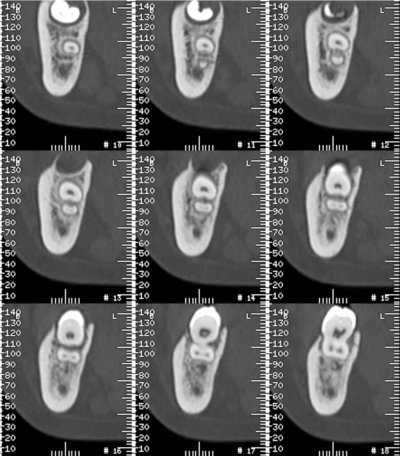

SCANNER DENTAIRE (DENTALSCANNER)

Les nouvelles générations de scanner permettent de faire une acquisition d’un volume global d’une partie du corps et de travailler à l’intérieur de ce volume en isolant une structure anatomique donnée et de l’explorer dans tous les plans de l’espace.

Grace à la technique de seuillage il est possible de dissocier progressivement les dents des structures osseuses environnantes dans le volume donné.